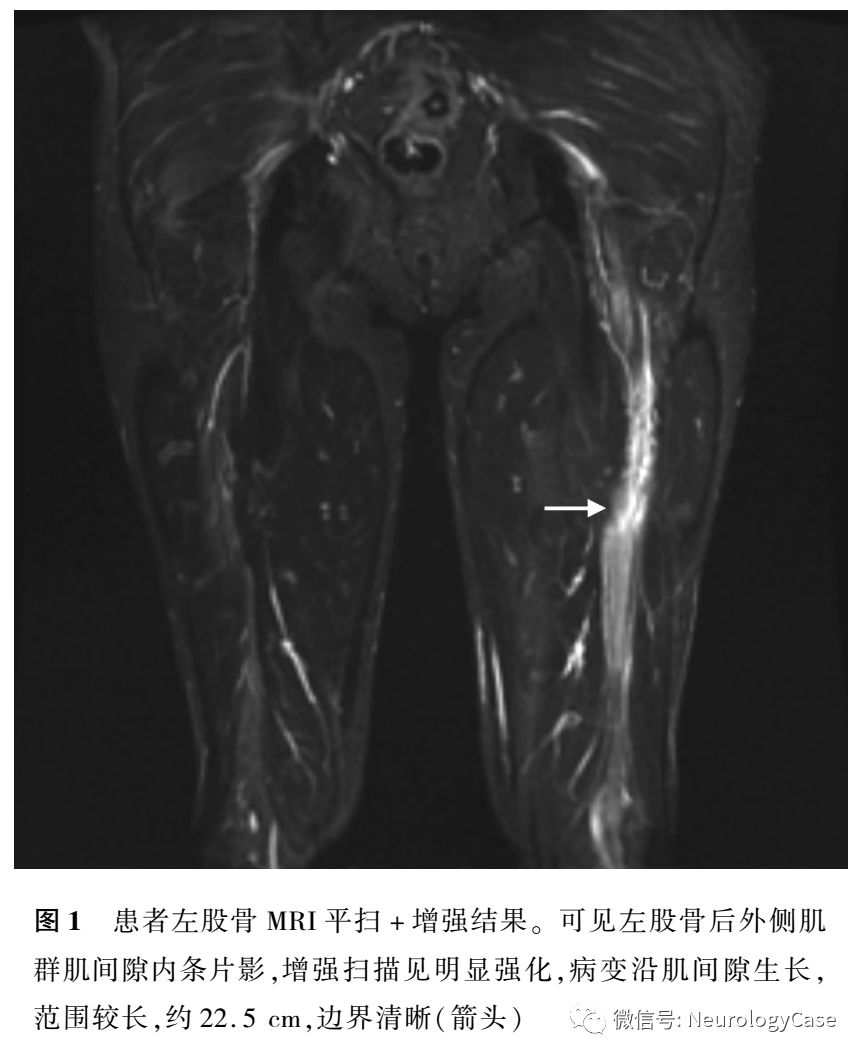

原發性睾丸淋巴瘤復發致以坐骨神經痛為表現的神經淋巴瘤一例 神經科病例擷英拾粹 微文庫